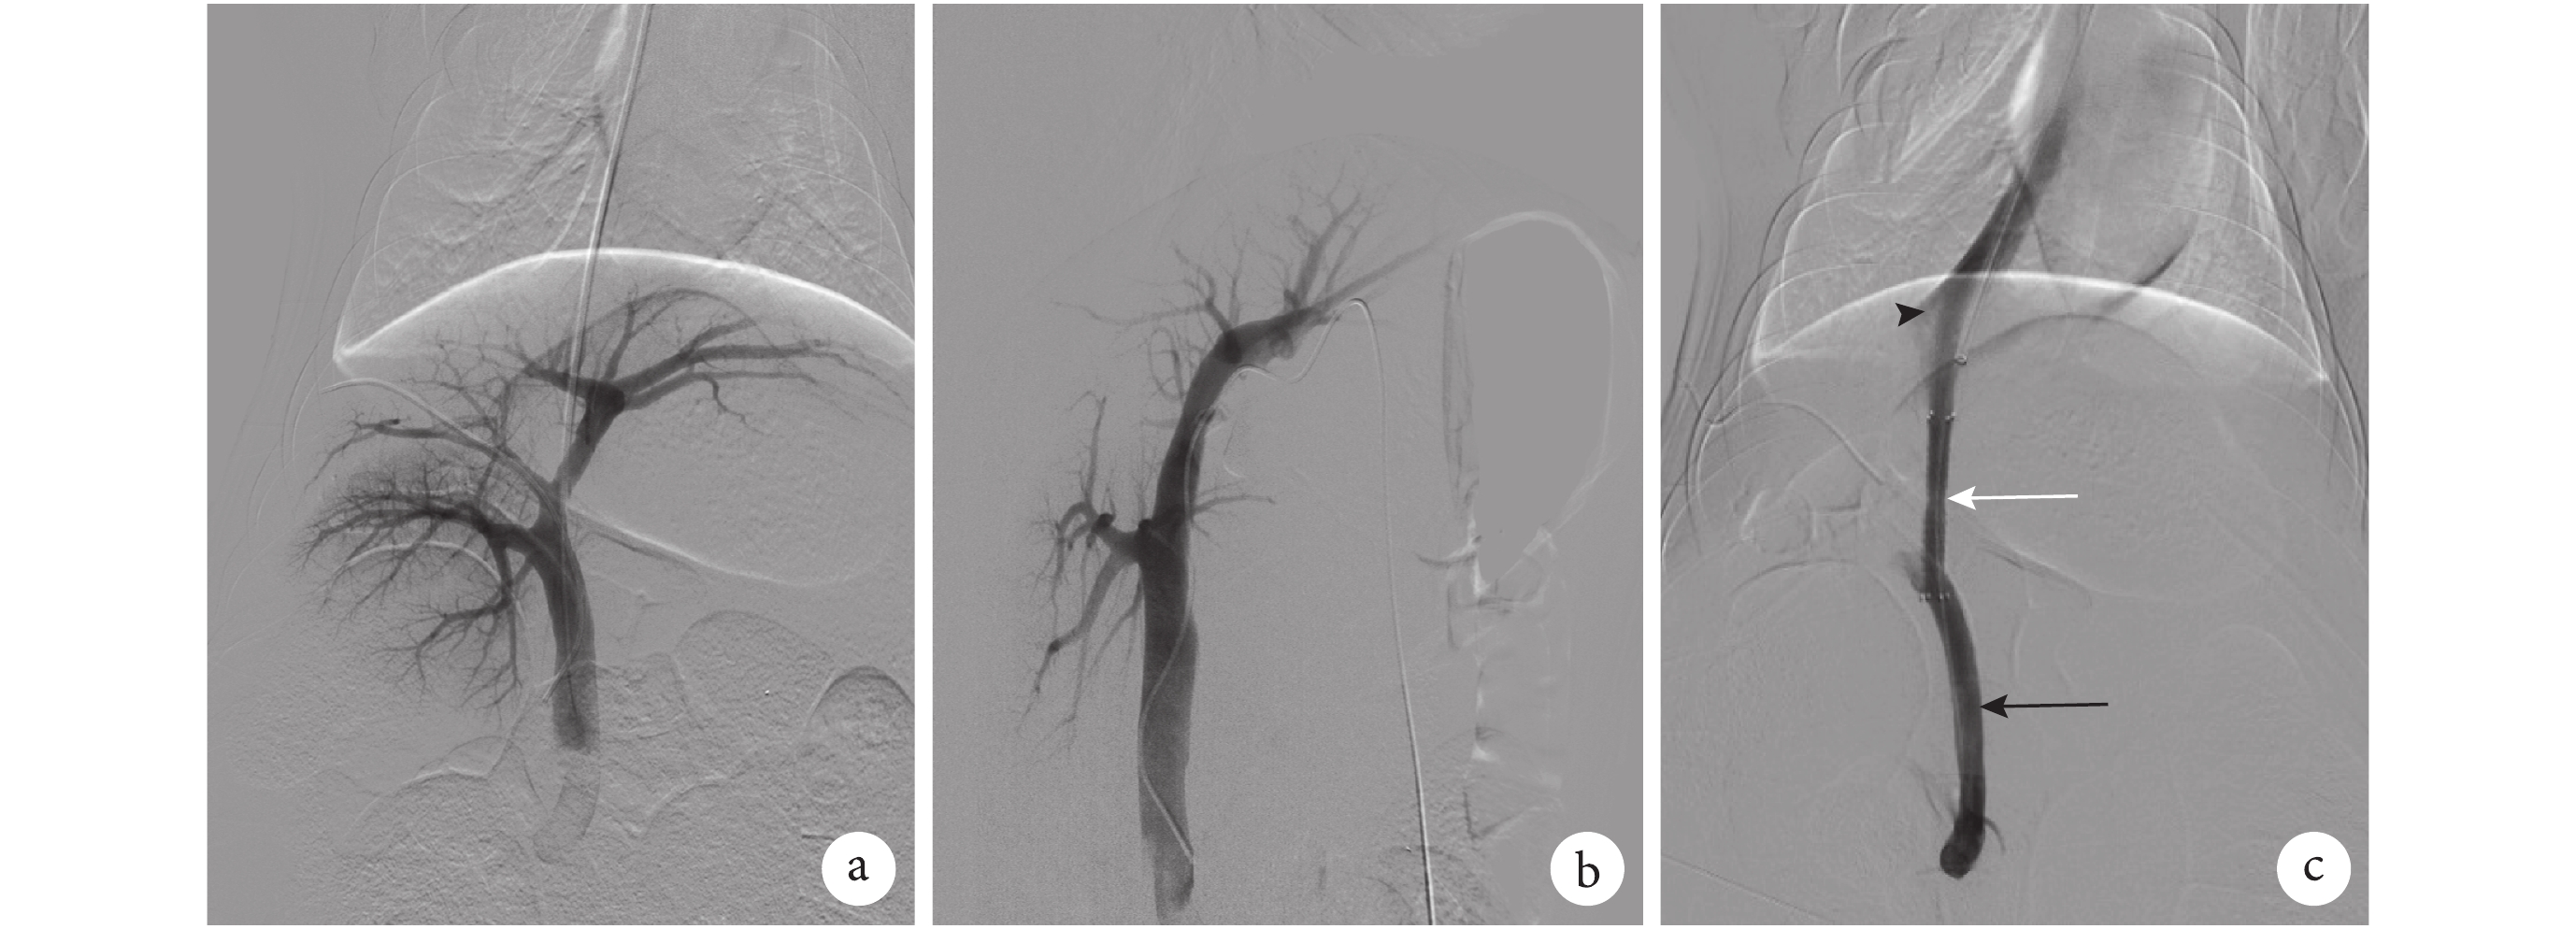

1.2.1 靶導管置入 實驗豬禁食禁飲 24 h,經耳緣靜脈注射 3% 戊巴比妥鈉(商品名:Nembutal),劑量 1 mL/kg 體質量,肌肉注射 25% 頭孢曲松鈉 2 g(商品名:英派琦)。取仰臥位,頸部及肝區備皮,5% 聚維酮碘溶液(商品名:艾利克)消毒,常規鋪巾。超聲引導下,以 22 G Ghiba 套管針(美國 COOK 公司)經皮穿刺肝內門靜脈分支,拔出針芯,在 X 射線引導下,將 0.018 英寸導絲送入門靜脈主干,退出外套管,沿導絲送入 5F 外鞘,交換 Amplatz 硬導絲(美國 Boston Scientific 公司),沿 Amplatz 硬導絲置入 5F 豬尾導管(美國 COOK 公司)至門靜脈主干作靶導管,測量門靜脈壓力并行正、側位門靜脈造影(圖 1a、1b)。經導管注射 5 000 U 低分子肝素鈣(商品名:賽博利)。

圖1

門靜脈及分流道造影

1.2.2 建立分流道 超聲引導下,經右側頸內靜脈置入 RUPS-100 穿刺系統(美國 COOK 公司)至下腔靜脈。在 X 射線引導下,對準門靜脈主干內靶導管進行穿刺,拔出針芯,經導管抽出靜脈血后,手推碘海醇注射液(商品名:歐乃派克)以確認成功穿刺門靜脈主干。沿導管置入 Amplatz 硬導絲至脾靜脈,拔出穿刺套件,沿 Amplatz 硬導絲置入 6 mm×8 cm Fluency 覆膜支架(美國 BARD 公司),釋放支架后交換球囊擴張導管(美國 COOK 公司),擴張分流道后,拔出球囊導管,沿 Amplatz 硬導絲置入 5F 豬尾導管(美國 COOK 公司)至門靜脈,行分流道造影(圖 1c),測量門靜脈及下腔靜脈壓力。術畢拔出導管,于頸內靜脈及經皮經肝穿刺處壓迫 20 min。